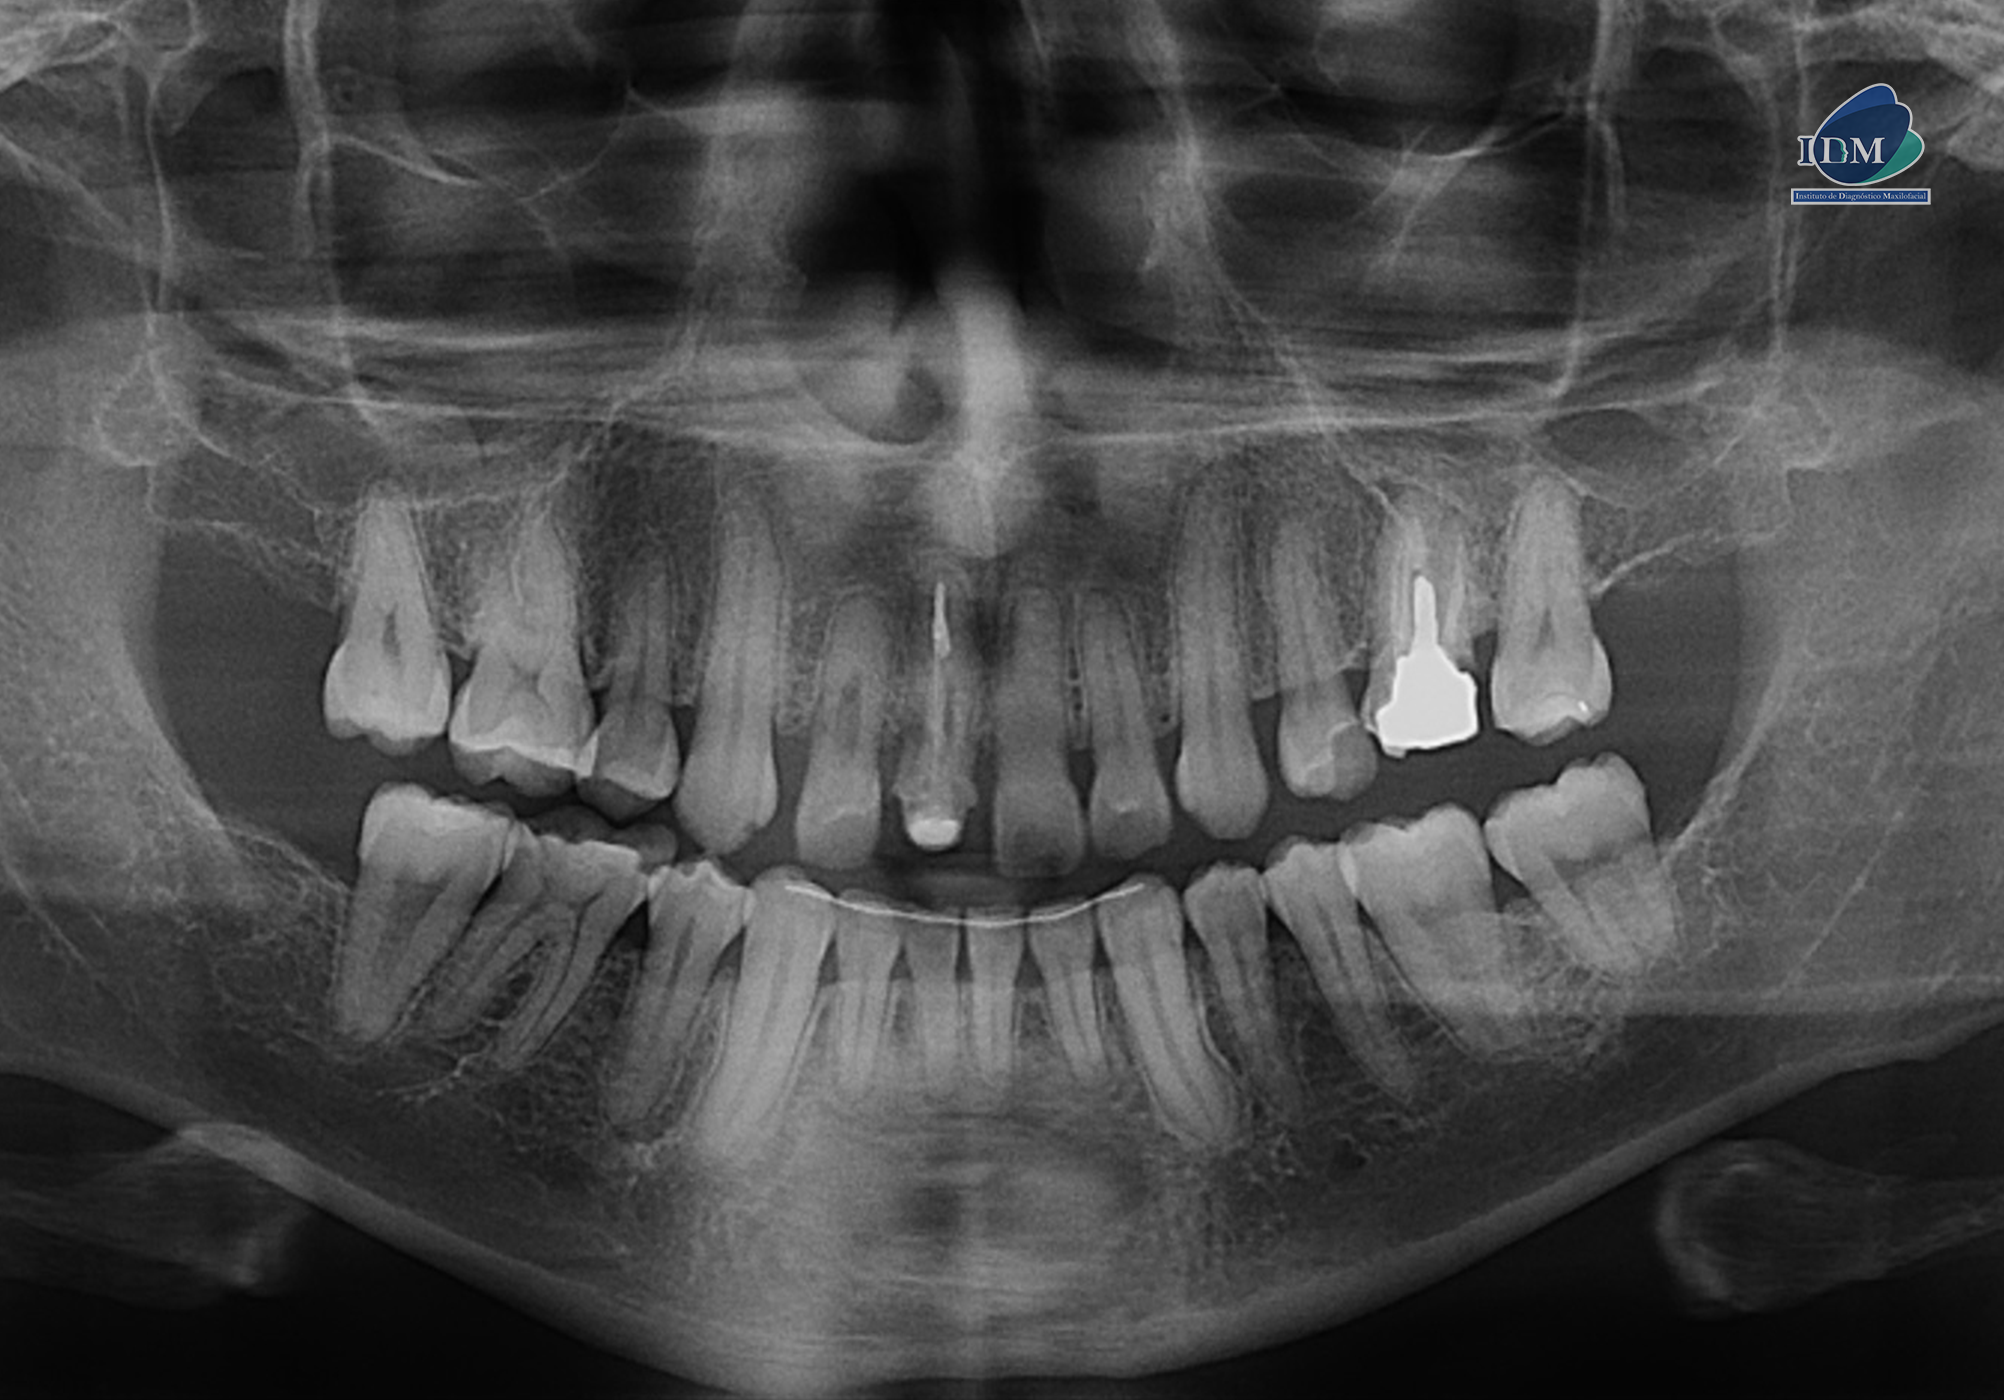

En las reconstrucciones 3D se representa de manera didáctica la reabsorción y obliteración de conducto radicular. (Figura 4).

RECONSTRUCCIÓN 3D

Conclusión:

- Características imagenológicas compatible con reabsorción radicular interna y obliteración de conducto radicular.